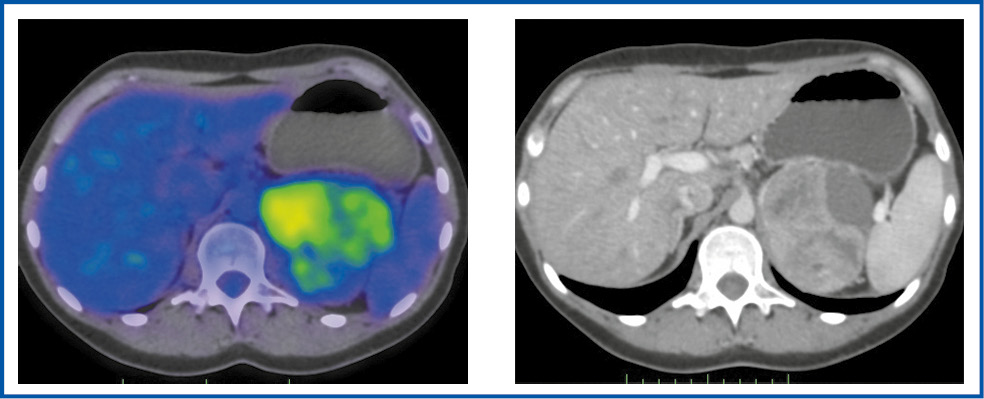

Неоднородную структуру опухоли наблюдали у 5 пациентов, кистозно-солидную – у 3, солидный характер образования – у 1 (рис. 1–4).

Количественный анализ результатов ПЭТ/КТ с 18F-ФДГ предусматривал определение ряда критериев, среди которых SUVmax 18F-ФДГ в области интереса: в ПОН, печени и селезенке, а также соотношение SUVmax в первичной опухоли к SUVmax в печени и селезенке. Приведенные показатели оценки поражения составляют основу диагностики и проведения дифференциальной диагностики ДО, а также первичных и вторичных ЗНО надпочечников.

Рис. 3. Больная К., 48 лет. В аксиальной проекции ПЭТ/КТ- и КТ-исследовании в правом надпочечнике определяется неоднородное солидное образование размером 98×64×95 мм с гиперфиксацией 18F-ФДГ, SUVmax – 14,67.

Fig. 3. Patient K., 48 years old. Axial view of PET/CT and CT imaging: in the right adrenal gland, there is a heterogeneous solid mass with a size of 98×64×95 mm and 18F-FDG hyper uptake; SUVmax is 14.67.

Согласно полученным данным диапазон колебаний его уровня составил 3,54–22,29, медиана – 10,0. Значение SUVmax≥10 наблюдали у 5 (55,6%) пациентов, а медиана в данной группе составляла 13,9. Максимальная величина SUVmax отмечена при двухсторонней локализации образований, достигая 22,29 (рис. 4), а минимальный его показатель – 3,54.